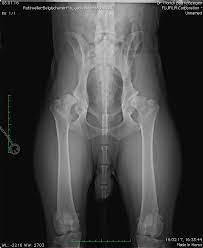

Abbau der knochensubstanz im hüftknochen wegen durchblutungsstörungen Wann geht an einer op kein weg vorbei? Man lässt sich operieren, wenn der film, den man von seinem leben sieht und die realität zu weit auseinanderklaffen. In der folgenden abbildung ist verdeutlicht, wie sich die verbesserung durch eine operation auswirkt: Es schützt und stabilisiert das knie. Hunderttausende menschen werden jedes jahr an hüfte oder knie operiert. Wann sollte man sich operieren lassen? Die am häufigsten durchgeführte therapie, um eine hüftgelenksarthrose gelenkerhaltend zu behandeln, ist die sogenannte umstellungsosteotomie. Der entscheid für die operation muss für sie stimmen. Aussagen wie da können wir nichts anderes mehr machen, als ein künstliches hüftgelenk einzusetzen zeugen von der ratlosigkeit der ärzte. In diesen fällen muss der orthopäde mit einer prothese, also einem künstlichen hüftgelenk, helfen. Eine arthritis kann zu schweren gelenksschädigungen führen. Bei den meisten patienten liegt hüftarthrose (coxarthrose) vor, rund ein viertel der patienten haben zuvor einen oberschenkelhalsbruch erlitten.

Der entscheid für die operation muss für sie stimmen. Wann benötigt ein patient mit hüftarthrose (coxarthrose) eine hüftprothese? Operiert man dagegen zu spät, ist. Eine op bei daumenarthrose kann auch sinnvoll sein, wenn betroffene in starkem ausmaß eine gute und feine beweglichkeit in der hand benötigen. Die arthrose ist die häufigste ursache für kniebeschwerden. Die einschränkung der lebensqualität, die durch die fortgeschrittene hüftarthrose verursacht wird, ist bei jeder person unterschiedlich ausgeprägt. Hunderttausende menschen werden jedes jahr an hüfte oder knie operiert. Es geht immer um lebensqualität, und die kann nur der. Bei diesen zahlen kann leicht der eindruck entstehen, dass ärzte einfach gerne operationen durchführen. Um den schmerzen zu entkommen, lassen sich 158.000 deutsche mit arthrose jedes jahr ein kunstknie einsetzen. Eine operation muss immer dann durchgeführt werden, wenn die gelenke der fußwurzelknochen nach einer fraktur disloziert sind, also die normalen anatomischen verhältnisse nicht mehr vorhanden sind. Bei diesem verfahren wird eine fehlstellung am beschädigten gelenk beseitigt, um die natürlichen achsenverhältnisse in der hüfte wiederherzustellen. Sie ersetzt entweder das komplette gelenk oder nur einen teil davon.

Dänische forscher haben das für und wider nun in einer hochwertigen vergleichsstudie unter die lupe genommen. Zuletzt aktualisiert am freitag, den 30. Sie bestimmen, wann für sie der richtige zeitpunkt für ein künstliches hüftgelenk gekommen ist. Eine operation des daumengelenks ist immer dann erforderlich, wenn die funktionseinschränkungen des daumengelenks fortgeschritten sind. Bei diesem verfahren wird eine fehlstellung am beschädigten gelenk beseitigt, um die natürlichen achsenverhältnisse in der hüfte wiederherzustellen. Dies ist dann der fall, wenn alle konservativen maßnahmen zu behandlung des gelenkverschleißes keine wirkung mehr zeigen und der leidensdruck der betroffenen durch diese nicht mehr weiter gebessert werden kann. Bei dem vorliegen einer kniearthrose kann es nötig werden, dass eine operation durchgeführt wird. Eine erbliche fehlstellung der hüfte führt zu vorzeitigem verschleiß;

Obwohl das inzwischen in fachkreisen bekannt. Zuletzt aktualisiert am freitag, den 30. Sie muss ja nicht zwingend operiert werden. Wann sollte man sich operieren lassen? Bei dem vorliegen einer kniearthrose kann es nötig werden, dass eine operation durchgeführt wird. Wenn sie noch keine deutlich einschränkenden schmerzen verursachen, rechtfertigen die arthroseveränderungen keinen operativen eingriff. Sie bestimmen, wann für sie der richtige zeitpunkt für ein künstliches hüftgelenk gekommen ist. Abbau der knochensubstanz im hüftknochen wegen durchblutungsstörungen Sie ersetzt entweder das komplette gelenk oder nur einen teil davon. Operiert man zu früh, kann das potenzial einer verbesserung nicht voll ausgeschöpft werden. Nach der operation dauert es einige wochen bis monate, bis man sich von dem eingriff erholt hat und das künstliche gelenk für die meisten aktivitäten beweglich und stabil genug ist. Als folge von fehlbelastungen, unfällen, altersbedingtem knorpelabrieb, aber auch übergewicht weist der gelenkknorpel im fortgeschrittenen stadium deutliche abnutzungserscheinungen auf. Dabei werden die geschwächten muskeln wieder aufgebaut.